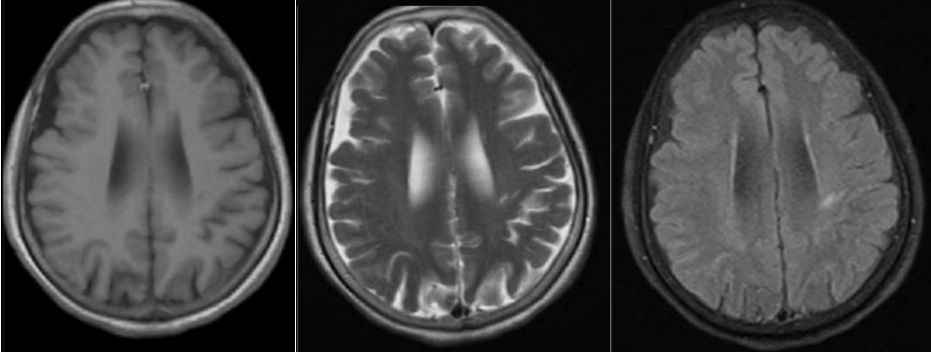

发病24小时磁共振:

答案:脑型脂肪栓塞综合征。患者做了自体脂肪填充术。脂肪栓塞综合征(fat embolism syndrom,FES)是指直径为10~40μm的血管内脂肪颗粒阻塞血管腔而引起的一系列病理生理改变的临床综合征。FES常发生于骨创伤及骨手术病人。FES潜伏期为6~24h,FES 的典型三联征为低氧血症、意识障碍和瘀斑。